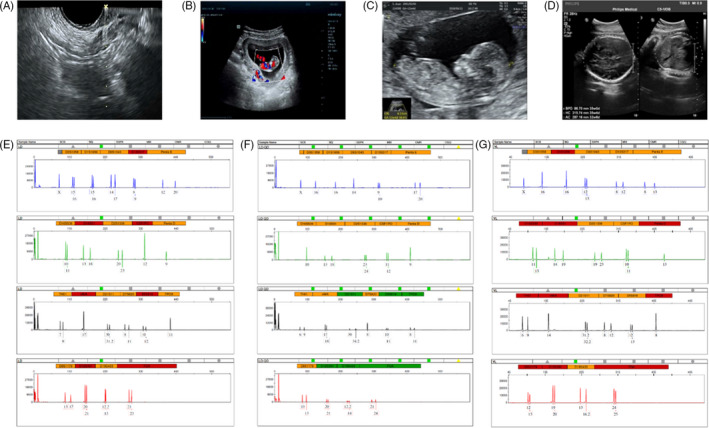

取卵和妊娠特征

收集了15名接受取卵的患者的基本特征,包括取卵周期、胚胎移植和妊娠次數。一般來(lái)說(shuō),四個(gè)胎兒沒(méi)有出生缺陷,三個(gè)胚胎來(lái)自ICSI的受精類(lèi)型,而最后一個(gè)是自然受孕的。1例術(shù)中超聲掃描顯示,在經(jīng)陰道超聲(TVUS)引導下,卵巢未見(jiàn)間質(zhì)增生或其他異常卵巢結構(圖2A)。這名婦女在體外受精后成功懷孕,并在第8周進(jìn)行了基本產(chǎn)前程序的超聲掃描(圖2B),第13周(圖2C) 和第32周 (圖二維) 顯示正常的胎兒發(fā)育。微衛星位點(diǎn)分析顯示,胎兒(圖2F)與母親有遺傳關(guān)系(圖2E) 供體UCMSC以外的其他人(圖2G)。